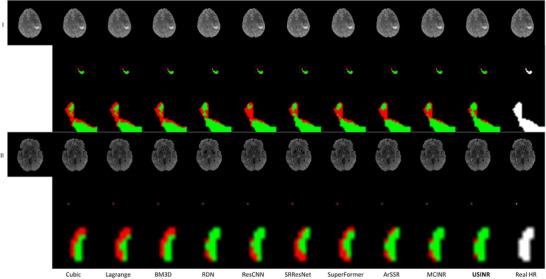

USINR was evaluated on three datasets, including IXI, BraTS, and an in-house abdominal dataset. It achieved state-of-the-art performance on all of them. For example, on the BraTS dataset, USINR was trained on 1151 paired training samples (for universal anatomical mapping) and tested on 50 patients. It achieved average SSIM, PSNR, and LPIPS scores of 0.9656, 37.12, and 0.0214, respectively, significantly outperforming the published state-of-the-art method SuperFormer, whose corresponding scores were 0.9488, 35.83, and 0.0388. Furthermore, USINR can complete patient-specific training in less than one minute, rendering it a favorable solution in time-constrained ART workflows. In addition to large-scale dataset evaluations, a case study was conducted on an in-house patient at UT Southwestern Medical Center. This case study included two MRI scans (a prior scan for plan simulation and a new one for on-board imaging) from a single patient with a long interval between two scans, during which the tumor size underwent a significant change. Despite these substantial anatomical changes between prior and on-board imaging, USINR was able to accurately capture the change in tumor size, highlighting its robustness for clinical applications.

USINR在三个数据集上进行了评估,包括IXI、BraTS和一个内部腹部数据集。在所有这些数据集上,它都取得了领先的性能。例如,在BraTS数据集上,USINR在1151对训练样本(用于通用解剖映射)上进行训练,并在50名患者上进行测试。它分别实现了平均结构相似性指数(SSIM)、峰值信噪比(PSNR)和学习感知图像补丁相似度(LPIPS)分数为0.9656、37.12和0.0214,显著优于已发表的领先方法SuperFormer,其相应分数分别为0.9488、35.83和0.0388。此外,USINR可以在不到一分钟的时间内完成患者特异性训练,使其成为时间受限的ART工作流程中的理想解决方案。除了大规模数据集评估外,还在德克萨斯大学西南医学中心的一名内部患者身上进行了案例研究。该案例研究包括来自一名患者的两次MRI扫描(一次用于计划模拟的先验扫描和一次用于机载成像的新扫描),两次扫描之间间隔较长,在此期间肿瘤大小发生了显著变化。尽管先验成像和机载成像之间存在这些显著的解剖结构变化,USINR仍能够准确捕捉肿瘤大小的变化,突出了其在临床应用中的稳健性。